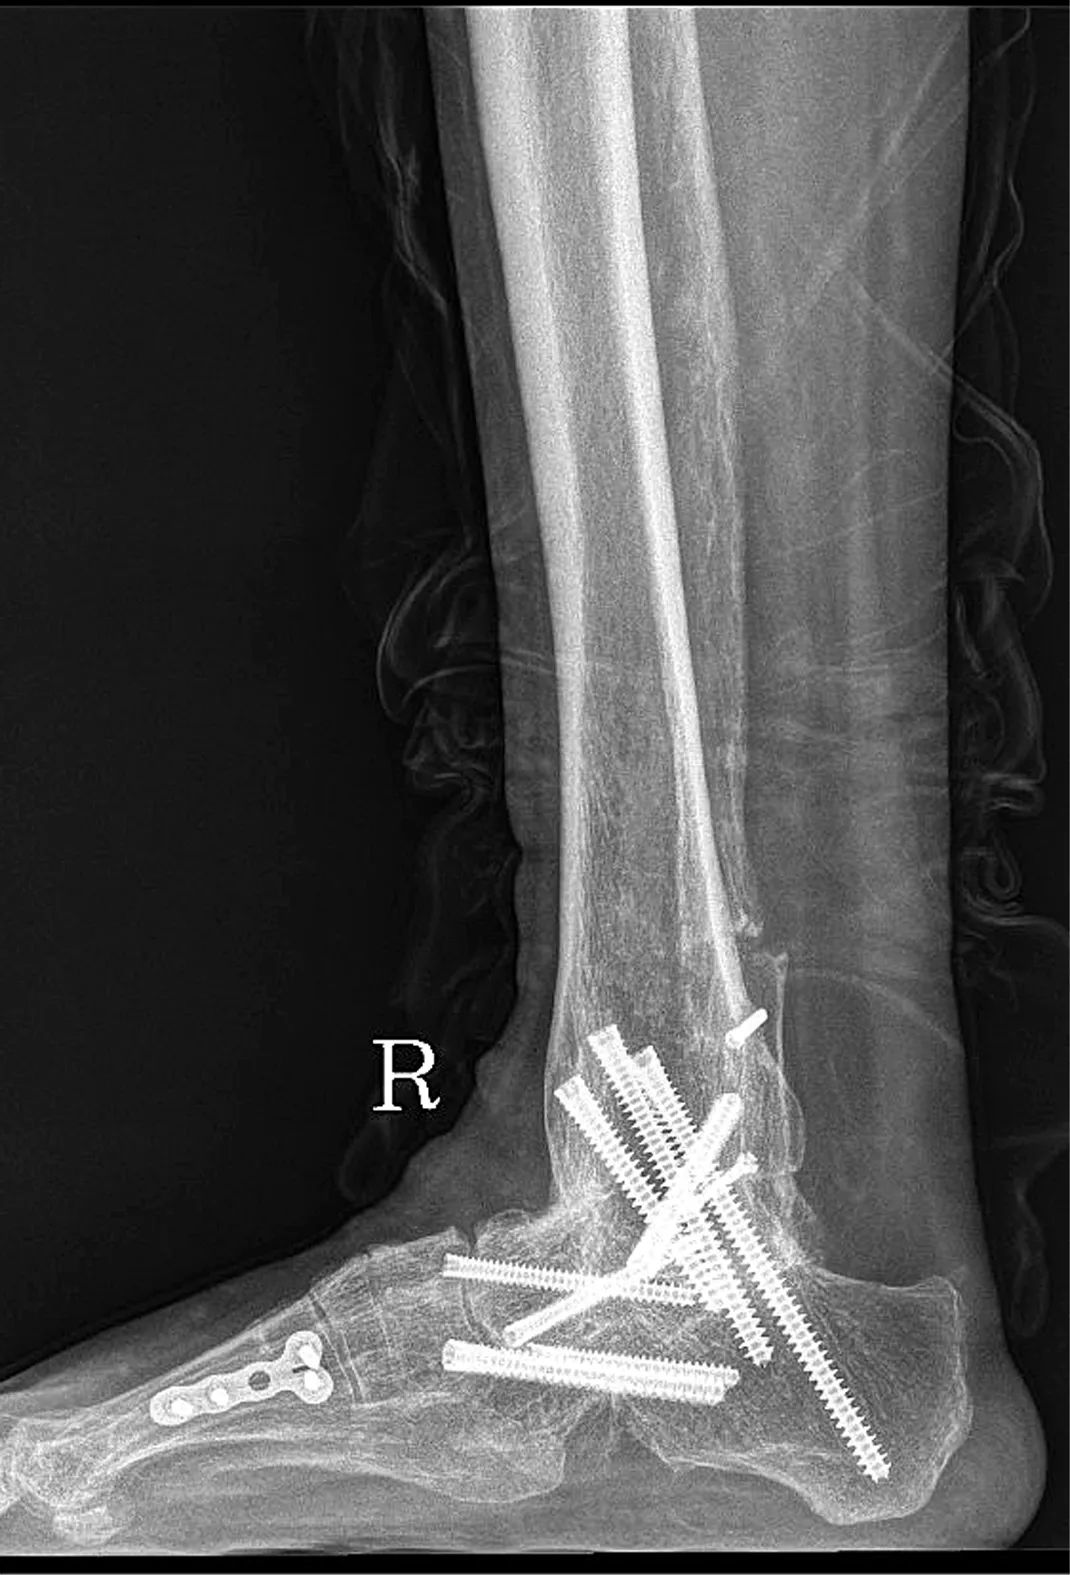

为最大限度提升术后效果,梁晓军为患者进行了全面完善的术前检查和准备。2月28日,肖某玲迎来了手术日。手术打开已经生长在一起的骨头,将原来的内固定取出,重新松解周围软组织、定位踝关节开放截骨线,最后将人工假体成功植入。“融合术后原来的两块骨头就变成一块了,要重新找到关节面,精确打开,再松解周围组织,手术要求非常高,好在手术顺利完成了。”梁晓军说,术后,肖某玲的踝关节就可以重新活动了。